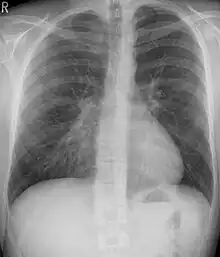

Pleural effusion

A pleural effusion is an accumulation of fluid inside the pleural space. If this collection of fluid gets large enough, it can also push structures in the chest away from it and cause a mediastinal shift. However, a pleural effusion can also pull mediastinal structure towards itself. If this is the case, then there is an underlying condition causing collapse of the lung on that side. An example is a tumor obstructing a bronchus and causing lung collapse and pleural effusion.[3]